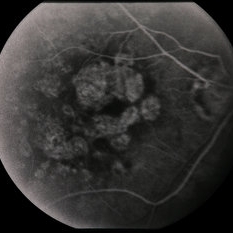

---thumb.jpg/image-square;max$300,300.ImageHandler) Age Related Macular Degeneration - Geographic Atrophy

Age Related Macular Degeneration - Geographic Atrophy

May 3 2013 by Suber S. Huang, MD, MBA, FASRS

Geographic Atrophy.

Imaging device: Retina Diseases Imaging Reading Center

Condition/keywords: advanced geographic atrophy, atrophic scar, atrophic spot, geographic atrophy, macula lesion, pigment epithelial atrophy, red-free, window defect